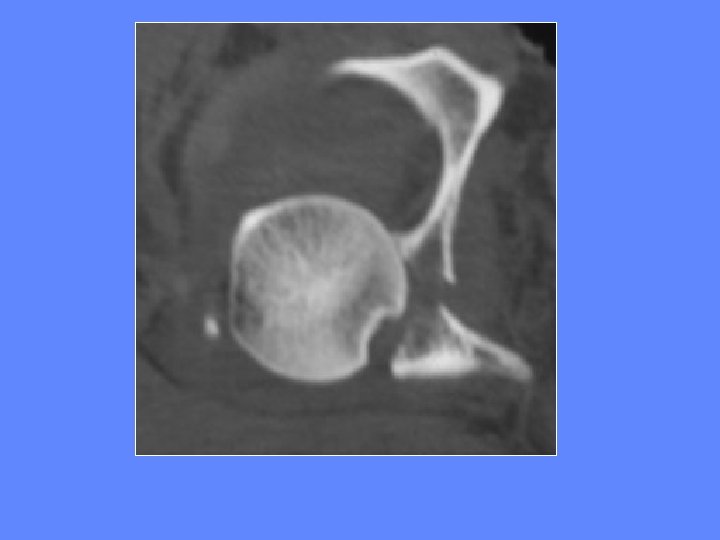

Fractures de la paroi postérieure Elles sont les plus fréquentes accompagnent en général une luxation postérieure de la hanche

Fractures de la paroi postérieure luxation postérieure de la hanche

TDM luxation postérieure de la hanche

Incarcération d’un fragment intra-articulaire